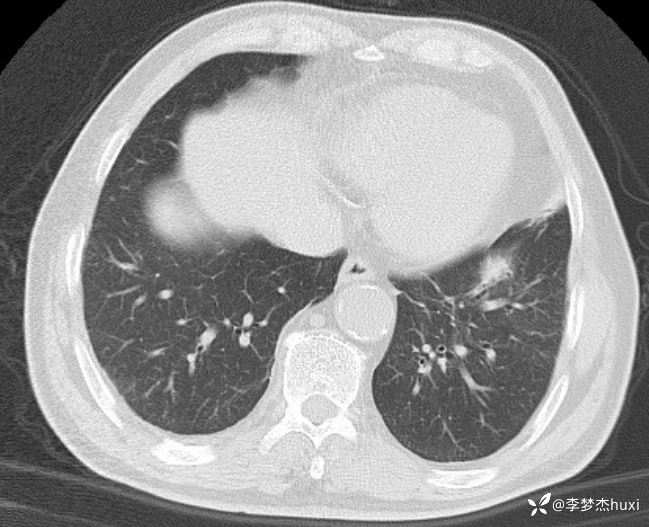

男性63岁,热伴胸痛4天,胸部CT示双肺多发结节,考虑什么疾病?

【现病史及既往史】: 1.患者老年 男,患者于入院前4天无明显诱因出现发热,具体体温不详,伴右侧胸痛,无放射痛,偶有咳嗽、无明显咳痰,无鼻塞,无咽痛,无胸闷、憋气,无恶心、呕吐,无腹痛、腹泻,无尿急、尿频、尿痛,院外口服退热药物治疗(具体不详),症状好转,今患者及家属为进一步诊治前来我院就诊,门诊查胸部CT:双肺炎症;双肺间质性改变;右肺上叶肺大疱?纵隔内肿大淋巴结,部分钙化;主动脉及冠状动脉壁钙化;双侧胸膜局部增厚;右侧第9、10肋骨欠规整?;右侧胸壁术后改变,双肺实性结节,建议复查或肺结节门诊检查,故门诊以“社区获得性肺炎,非重症”收入院。

【临床诊断】: 社区获得性肺炎,非重症。